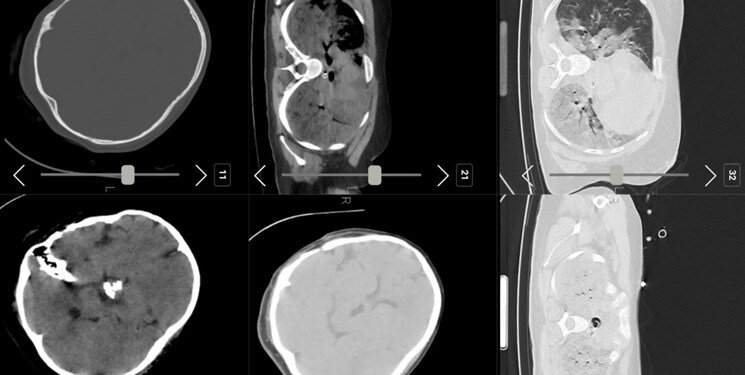

به گزارش همشهری آنلاین، در بیانیه سازمان پزشکی قانونی آمده است: با استناد به مدارک پزشکی بیمارستانی، بررسی سی تی اسکن مغز و ریه، نتایج معاینات ظاهری جسد و کالبدشکافی و آزمایشات آسیب شناسی فوت مرحوم مهسا امینی ناشی از اصابت ضربه به سر و اعضا و عناصر حیاتی بدن نبوده است.

شرح مختصری از گزارش علت فوت مرحومه مهسا امینی ارائه شده به مرجع قضائی که بر اساس پرونده بیمارستانی عمل جراحی کرانیوفارنژیومای مغز در بیمارستان میلاد در سال ۱۳۸۶، پرونده درمانی بیمارستان کسری در زمان منتهی به فوت، شرح معاینه ظاهری جسد و کالبدگشایی، نتایج آزمایش‌های سم‌شناسی و آسیب‌شناسی، تحقیقات قضایی و کمیته‌های کارشناسی متعدد تخصصی و فوق تخصصی تنظیم یافته است به شرح ذیل اعلام می‌شود:

متوفیه پس از عمل جراحی تومور کرانیوفارنژیومای مغزی در سن ۸ سالگی دچار اختلال در محور مهم هیپوتالاموس ـ هیپوفیز و غدد تحت فرمان آن (از جمله آدرنال و تیروئید) شده است. به علت این بیماری زمینه‌ای متوفیه تحت درمان با داروهای هیدروکورتیزون، لووتیروکسین و دسموپرسین بوده است.

ایشان در تاریخ ۱۴۰۱/۶/۲۲ از ساعت ۱۹:۵۶ بطور ناگهانی دچار افت هوشیاری شده و متعاقب آن بر زمین می‌افتد که با توجه به بیماری زمینه ای، متوفیه توانایی لازم جهت جبران و تطابق با وضعیت ایجاد شده را نداشته، لذا در شرایط مذکور دچار اختلال ریتم قلب و کاهش فشار خون و متعاقب آن کاهش سطح هوشیاری شده که به دلیل انجام عملیات احیای قلبی ـ تنفسی غیرموثر در دقایق حساس اولیه، دچار هیپوکسی شدید و در نتیجه آسیب مغزی شده است، علی رغم برگشت عملکرد قلبی متعاقب عملیات احیای پرسنل اورژانس، حمایت تنفسی انجام شده کارساز نبوده و با وجود انتقال ایشان به بیمارستان و زحمات کادر درمانی بیمارستان کسری، بیمار به علت نارسایی چند ارگانی (M.O.F) ناشی از هیپوکسی مغزی در تاریخ ۱۴۰۱/۶/۲۵ فوت می‌نماید.

لازم به ذکر است با استناد به مدارک پزشکی بیمارستانی، بررسی سی. تی اسکن مغز و ریه، نتایج معاینه ظاهری جسد و کالبدگشایی، آزمایشات آسیب شناسی، فوت نامبرده ناشی از اصابت ضربه به سر و اعضا و عناصر حیاتی بدن نبوده است.